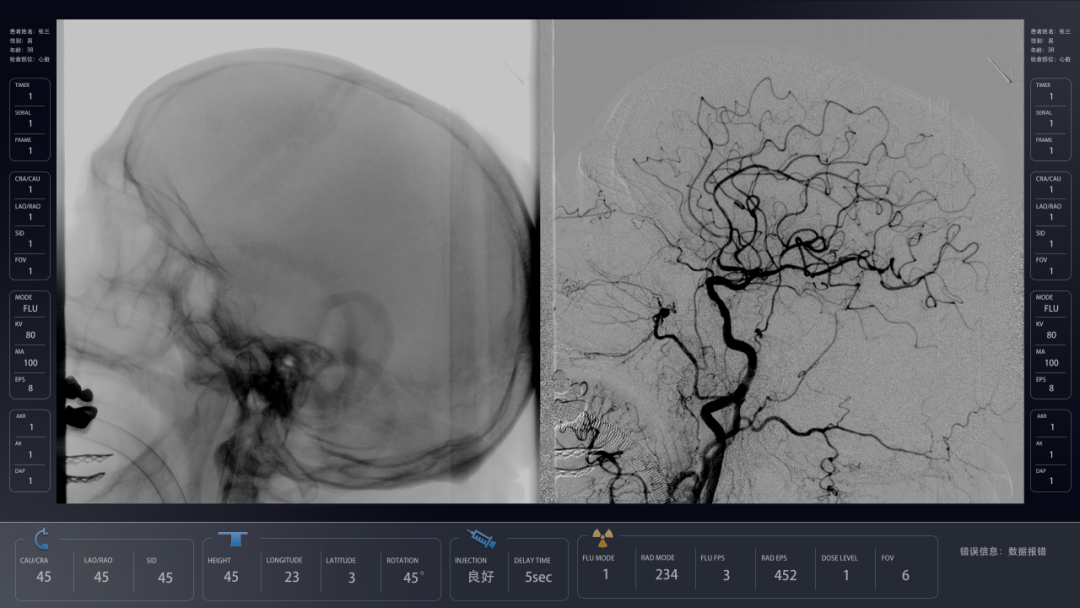

唯迈医疗成立于2014年,是专注于介入影像全流程管理的国家高新科技企业,提供“眼手脑”一体的介入全流程管理方案,覆盖大型血管造影机(DSA)、移动血管造影机(中C)、外科C型臂(小C)及小C一体机、介入手术机器人等介入产品全线,并实现各产品的多技术协同。其响应国家“十四五”规划发展高端医疗设备,从研发、性能、理念等均做到了“以科技创新,为生命护航”。其中,其自主研发的极光DSA率先获得欧盟CE证,实现国产高端DSA医疗设备在海外市场从0到1的突破。这是唯迈医疗继成功控股意大利EC公司后,携极光强势进军海外市场,全球战略布局又迈出的重要一大步。本次CMEF,唯迈医疗将携介入全线新国货亮相12号馆12C15展位。唯迈医疗,作为高端医疗领域代表,其围绕微创介入治疗领域深耕多年,在海内外都取得了突破性进展,实现了国产DSA技术的突破,真正意义上实现了国产替代。此次亮相CMEF大会的极光智能七轴落地式DSA,更是唯迈医疗旗下的拳头国货——拥有多项专利的创新DSA智能血管造影机。

极光——全新一代落地式智能七轴平板DSA

超广扫描范围,轻松投照病患全身不同部位,且占地面积更小,广泛用于神经、心脏、肿瘤、外周(妇科、血管外科、消化等)各临床科室,满足复合介入手术的需求。

多重手段结合智能算法,呈现高清图像的同时剂量最低化,有效降低辐射伤害,保护医护和病患。